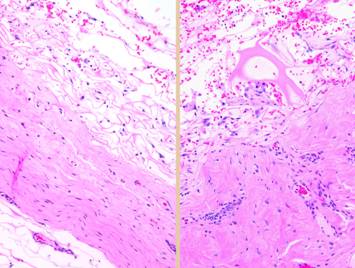

Left, a microscope image of normal wound healing.  The structure shown here is the prototypical wound.  Details of the structure and process will be explained in following panels.  Right, the microscopic appearance of fully regenerated Integra-CG matrix, the details likewise to be explained in following panels.  Even without explaining or focusing on specific details, the dissimilarity of the two can be appreciated.  Angiocytes and fibroblasts, vessels and connectives – that is all there is to these two tissues.  However, by supplying different “rules” or “subroutines” for the interaction and assembly of these elements, two different biomaterials emerge.  The rules or routines are based on the circumstances, reaction-to-injury versus embryonic regeneration.  The results have very different physical properties and implications for daily life, functional adaptations, and potential need for ongoing medical care.

Pictured is matrix regeneration within a piece of Integra collagen-gag matrix.  It is no longer the non-living empty matrix placed on the original wound, but a fully restored living material.  The details of this process are now presented.  However, even without knowing the specific details, it can be appreciated that the structure, morphology, and patterns of this regenerated biological material are different than the microscopic structure of the normal post-inflammatory wound.  Normal wound healing is triggered by inflammation and then evolves according to its own “program” of how angiocytes and fibroblasts rebuild a stroma of blood vessels and connective mesh.  Integra suppresses inflammation, and thus the normal “wound healing program” is never turned on.  Integra “heals” by a fundamentally different mechanism analogous to embryonic tissue generation.  Its build to a state of complete regeneration is uniform throughout the matrix, distributed rather than stratified, and when complete, it has created a new material that has characteristics mostly like normal dermis and quite unlike scar.  The matrix coaxes the same two cells, angiocytes and fibroblasts, to make a new tissue of blood vessels and connective mesh in a patterned morphology that is profoundly different then scar.  The same cells, making the same elemental components, assemble them in a completely different pattern than wound healing and scar because the embryogenesis-and-stromal-generation “program” is entirely different than the healing-and-scar “program”.